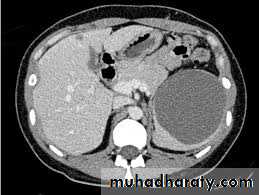

Splenic cysts

Splenic cysts are primary or secondary. Secondary cysts are more common and develop after splenic injuries, hence the name 'traumatic splenic pseudocysts' (no lining epithelium). Splenic traumatic pseudocysts may be totally asymptomatic but have a tendency to enlarge.The time interval between initial injury and presentation or diagnosis is extremely variable.

Some traumatic pseudocysts remain asymptomatic and are discovered accidentally during investigation by ultrasound.

Others develop abdominal pain and a palpable mass. Acute presentation with rupture is well treatment is only necessary for large symptomatic cysts after confirmation of the diagnosis by ultrasound or CT.

Spleen-preserving excision is possible unless the cyst is very large or presents acutely with rupture and bleeding documented.

• Surgicaltreatment is only necessary for large symptomatic cysts after confirmation of the diagnosis by ultrasound or CT.

• Spleen-preserving excision is possible unless the cyst is very large or presents acutely with rupture and bleeding

Splenic cyst